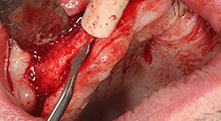

Брату: Ние използваме инструментите за събиране на костни блокове и разделяне на алвеоларни гребени. Ние също използваме Piezomed B6/B7 за остеотомия на наранени зъби и отстраняване на неуспешни импланти. Всички индикации, които изискват дълбоки, чисти разрези.

Брату: Ние предпочитаме да събираме кост от външната страна на гребена в задната част на долната челюст. След разрязване на меките тъкани, ние използваме новите триони, за да определим количеството кост, което ще събираме. С този подход, ние използваме трионите за цялата препарация в почти 80% от случаите. Може да използваме и други пиезо инструменти и накрая длето за мобилизиране на блока. Ние смятаме, че това е изключително ефективна хирургична техника.